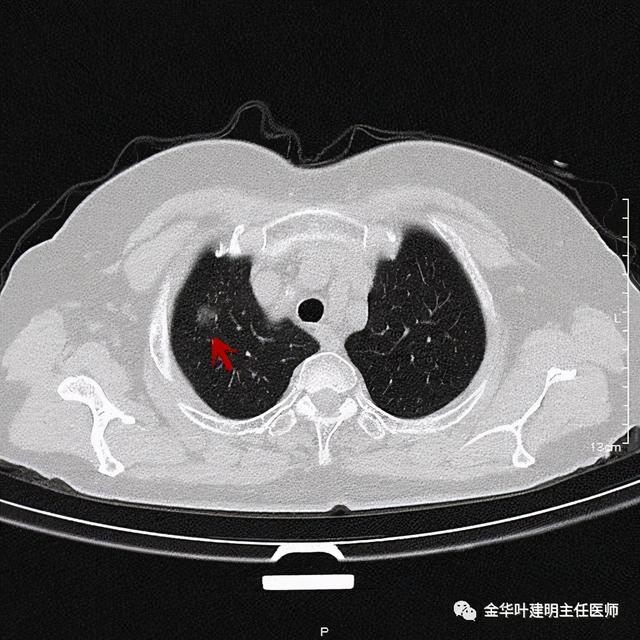

靶扫描更清楚显示瘤肺边界较清、分叶及密度不均杂乱 , 并有少许胸膜牵拉凹陷 , 当然考虑是肺癌 , 而且应该是浸润性腺癌了 。 其长径达2.5厘米!靶扫描还发现了平扫没被注意到的另一个病灶:

患者为女性 , 今年76岁 , 平时体质甚好 , 家务及地里劳动都胜任 , 头发仍乌黑(我自己倒有一半白发了) 。 肺功能与血气分析正常 。 CT检查图像如下:

可见右肺上叶混合磨玻璃结节 , 有明显分叶征 , 瘤肺边界虽然欠清楚 , 但轮廓比较清晰 。 看着也许会考虑炎性 , 但总觉得其比较僵硬 , 看去不舒服 。 这种病灶一是如果持续存在就极可能是肺癌 , 二是靶扫描显示更清晰的细节 , 如果瘤肺边界还是清楚的 , 也基本是肺癌 。 我们回顾发现其于2019年3月在我们医院做过CT平扫 , 当时报告如下: